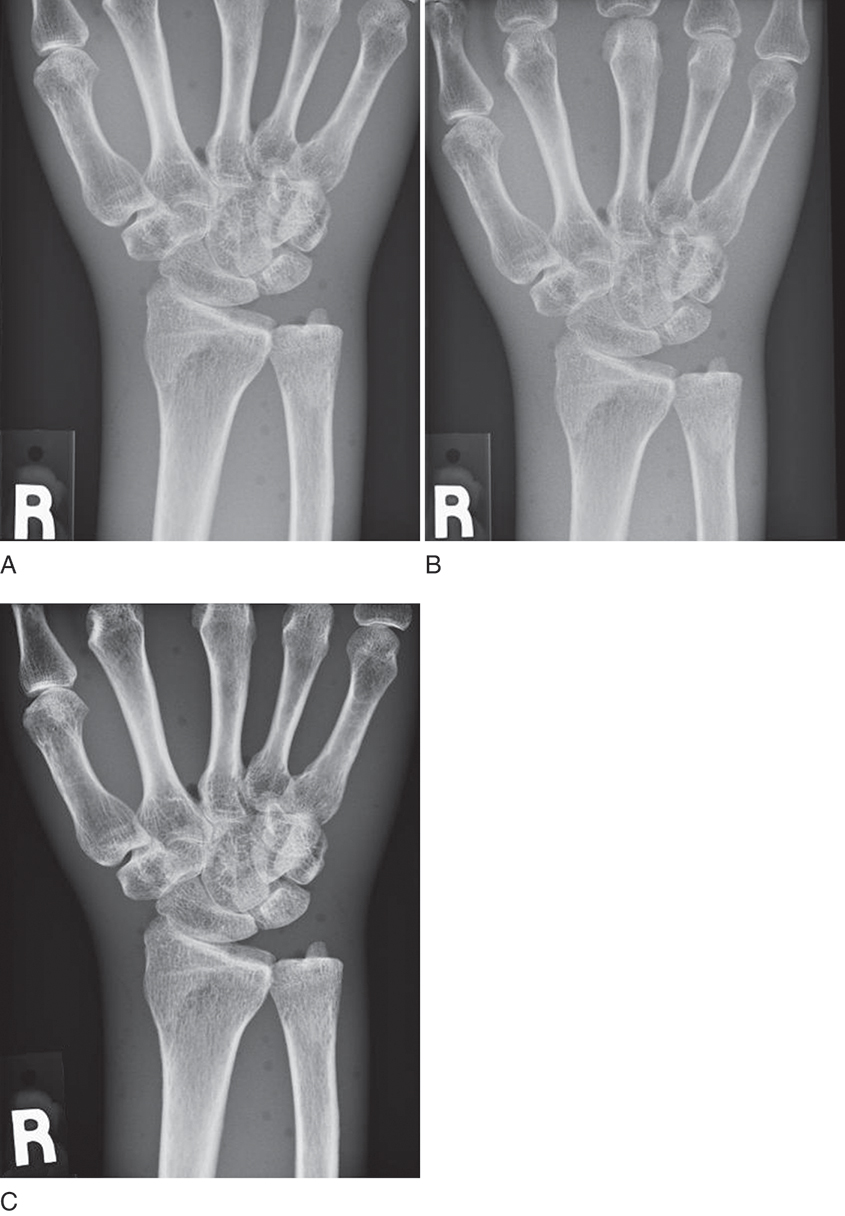

The amount of detail present in any image is known as its spatial resolution. Just as the crystal size and thickness of the phosphor layer determine resolution in film/screen radiography, phosphor layer thickness and pixel size help determine resolution in PSP. The thinner the phosphor layer, the higher the resolution. In film/screen radiography, resolution at its best is limited to approximately 10 line pairs (lp) per millimeter (mm). In general projection radiography PSP imaging, resolution is approximately 2.55 to 5 lp/mm, resulting in less detail. Resolution detail is also affected by the laser beam spot size (the smaller the diameter of the laser beam, the higher the spatial resolution), translation speed (slower speed allows more exposure to be detected), sampling frequency (the higher the sampling frequency, the more exposure detected), and the laser beam sweep in point beam readers (the tighter the sweep or the better shaping of the beam, the higher the resolution). However, because the bit depth, or the number of available shades of gray that can be displayed, is much higher, the difference in resolution is more difficult to discern. More tissue densities on the digital radiograph are seen, giving the appearance of more detail. For example, the fat pads on a lateral elbow are difficult to discern on a film image (Fig. 4.14A). Fat pads are a very important sign for the radiologists to see in pediatric elbow fractures. In the digital image, the fat pads are easily seen (see Fig. 4.14B). This is because of the ability to display more shades of gray, thereby making it possible to visualize more tissues of varying densities; this does not, however, mean that the digital image contains additional detail.

Two important factors should be considered when selecting the PSP imaging cassette: type and size. Most manufacturers produce two types of imaging plates: standard and high resolution. Cassettes should be marked on the outside to indicate high-resolution imaging plates. High-resolution imaging plates contain a thinner phosphor layer compared to the standard plates. The thinner layer results in greater image sharpness because of the reduced amount of light spreading in more lateral directions. When light spreads laterally, it causes the images to appear somewhat blurry. This occurs with any image capture system that involves the release of light. Typically, high-resolution imaging plates are limited to the smaller cassette sizes and are most often used for extremities, mammography, and other examinations requiring increased detail.

PSP digital images are displayed in a matrix of pixels (Fig. 4.19), and the pixel size is an important factor in determining the resolution of the displayed image. As a review from Chapter 2, if the matrix of an imaging system remains constant, as the field of view decreases, the pixel size also decreases and the spatial resolution of the image increases. Therefore the technologist should use the smallest field appropriate for the body part being imaged so that the pixel size will be at its smallest and the spatial resolution will be at its highest. Appropriate image plate selection for the examination also eliminates scatter outside the initial collimation by reducing the amount of imaging plate not being exposed, and this increases contrast resolution.